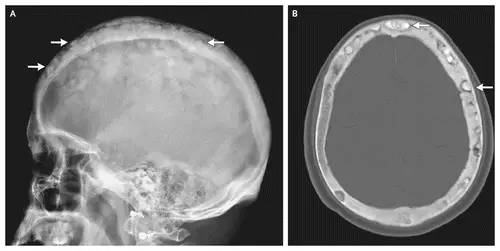

棉絮征

今天下班回家的路上看到一个买棉花糖(Cotton candy)的摊子,回来的时候就想到写一下“Cotton wool”这个征象,典型的棉绒征在国内应该不算常见,今天讲到的棉絮征是Paget(佩吉特)骨病中局限性钙质沉着在疏松的颅骨骨质中呈类似棉絮样改变的征象。

随着时间的推移病变可发生变化,治疗后溶骨区域可逆转。则某些特殊区域佩吉特骨病可出现特征性的改变,如脊柱受累时可出现“窗户框”现象,骨盆受累时可出现髋臼内陷及骶髂关节关节强直,颅骨受累时可出现骨质疏松性局限性钙质沉着和颅底凹陷症。